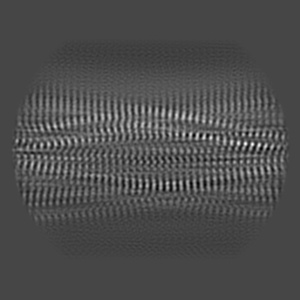

CTE typeIII tau filament

Helical reconstruction2.7 Å